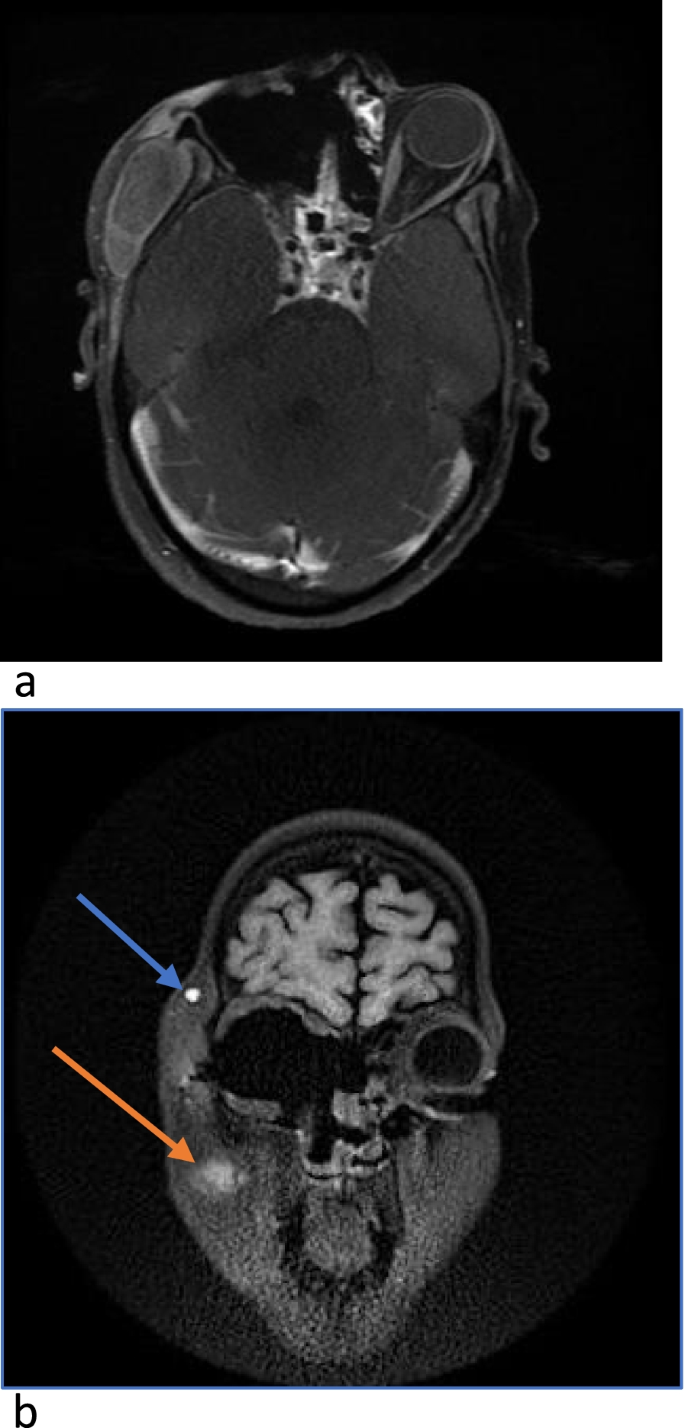

The patient had an uneventful postoperative period except for occasional hypokalemia due to amphotericin treatment for which potassium supplementation was given. Her Hb was 9.1 g/dl with a platelet count of 1.38X103/mm3. MRI was done after two weeks of surgery which showed complete recovery and there was no cavernous sinus involvement (Fig. 5a, b).

a, b Post-operative MRI shows right maxillary sinus widening with absent right eye globe and intraocular and extraocular muscles along with removed floor of orbit and absent nasal turbinates on the right side. Right orbit is seen communicating with sphenoid sinus on the right side. Fat suppressed hyperintensity seen in the right temporal fossa(blue arrow) and masticator space(red arrow) involving the right masseter and temporalis muscle. Hyperintensity is seen in the floor of the right maxillary sinus showing peripheral and septal enhancement on post contrast. Bilateral cavernous sinus are patent